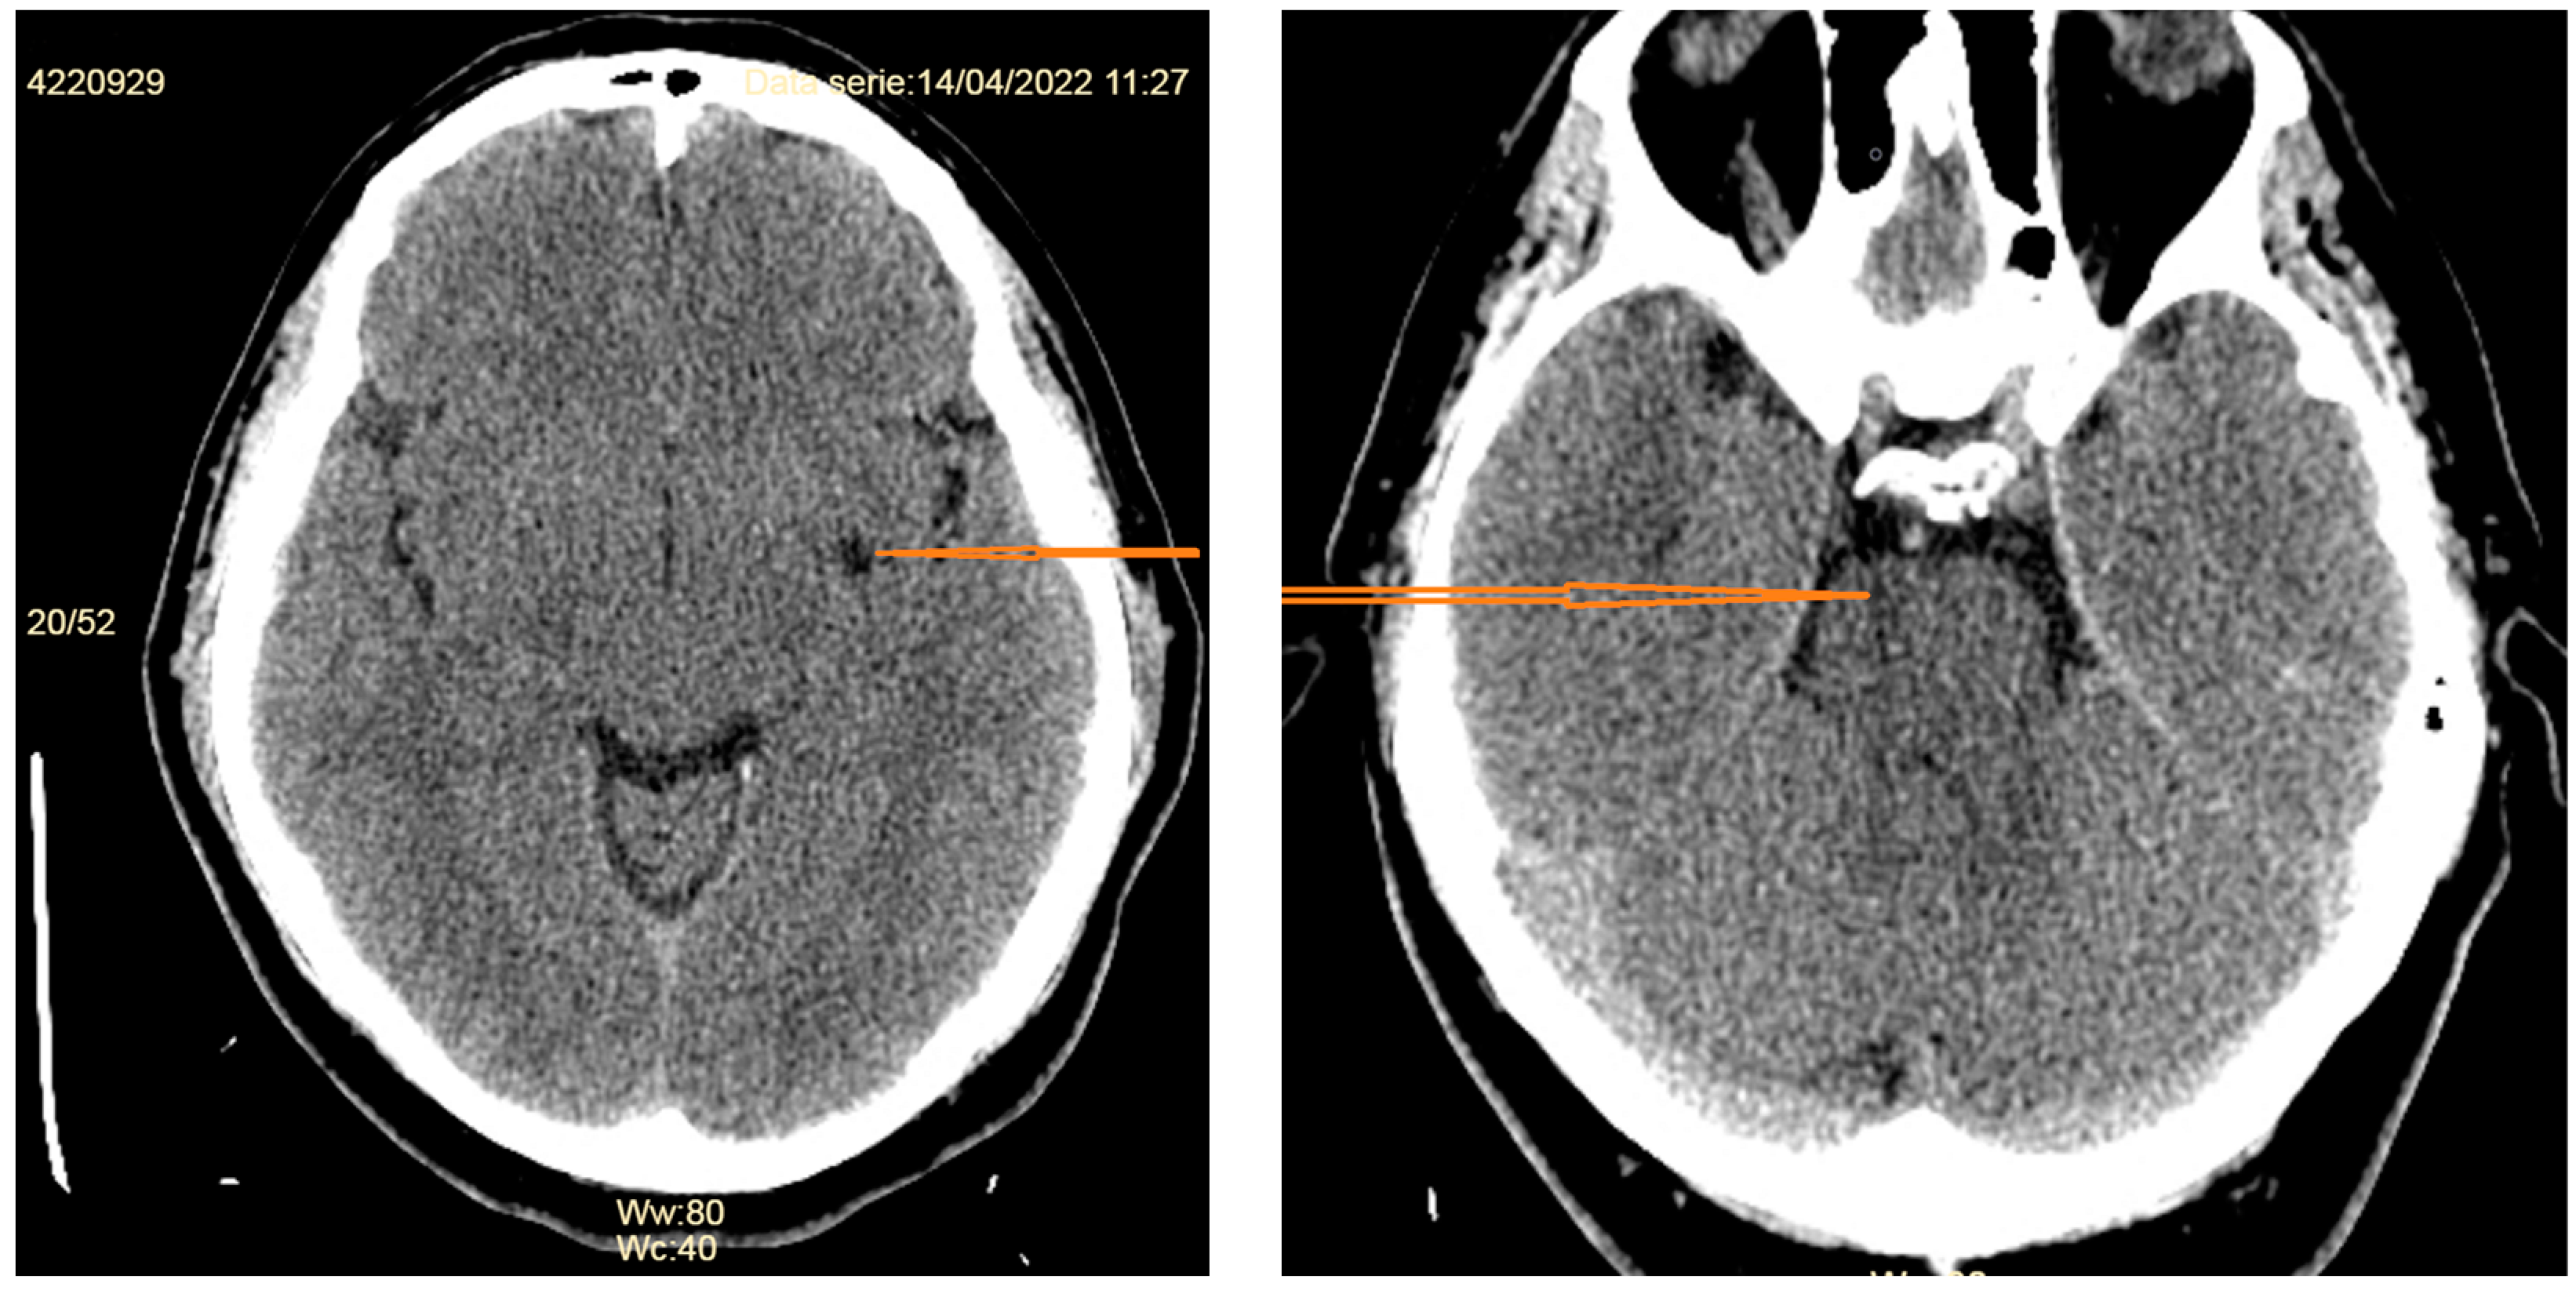

- -

- Diffuse pachymeningeal enhancement is detected in 73–83% of cases [19,32]. The dural thickening is typically diffuse and non-nodular. It needs to be differentiated from immunoglobulin 4 (IgG4)-related pachymeningitis [33], neurosarcoidosis (pachymeningeal and/or leptomeningeal enhancement is most prominent at the skull base) [34], infectious meningitis (in tuberculous meningitis the leptomeninges is usually also involved, while in syphilitic, cryptococcal meningitis or Lyme disease the involvement of other organs and systems may provide useful clues to diagnosis [35], or a series of immune-mediated conditions, such as rheumatoid arthritis, temporal arteritis, polyangiitis with granulomatosis, in which the dural enhancement is rather nodular [32].

- Subdural fluid collections—mostly bilateral hygromas—are described in 43–50% of patients [5,19]. Hygromas occur because of the enlargement of the subdural space secondary to the loss of the CSF, while subdural hematomas may be caused by tearing of the abnormally engorged and dilated cortical veins [32]. Drainage of these collections will not resolve them successfully if the CSF leak is not identified and treated [36].

- Signs of brain sagging include flattening of the ventral pons, effacement of the prepontine and perichiasmatic cisterns, or downward displacement of the cerebellar tonsils and brain stem [5,8], which may mimic Chiari type 1 malformation. However, in SIH, the tonsils maintain normal shape and do not descend more than 5 mm below the foramen magnum [37]. Moreover, the findings associated with syringomyelia would argue for the diagnosis of Chiari type 1 malformation [32].

- Dural venous sinus engorgement appears usually as a dilation of the transverse sinuses, which is subtle and often diagnosed retrospectively, by comparison of pre- and post-treatment images [5].

- Pituitary gland hyperemia leads to enlargement of the gland and can be mistaken for a pituitary adenoma [5].

- Reduced optic nerve sheath diameter and thickness (normal—4.4 mm; reduced to a mean of 3.4 mm) is best measured on coronal T2-weighted images or with transorbital ultrasonography [38].